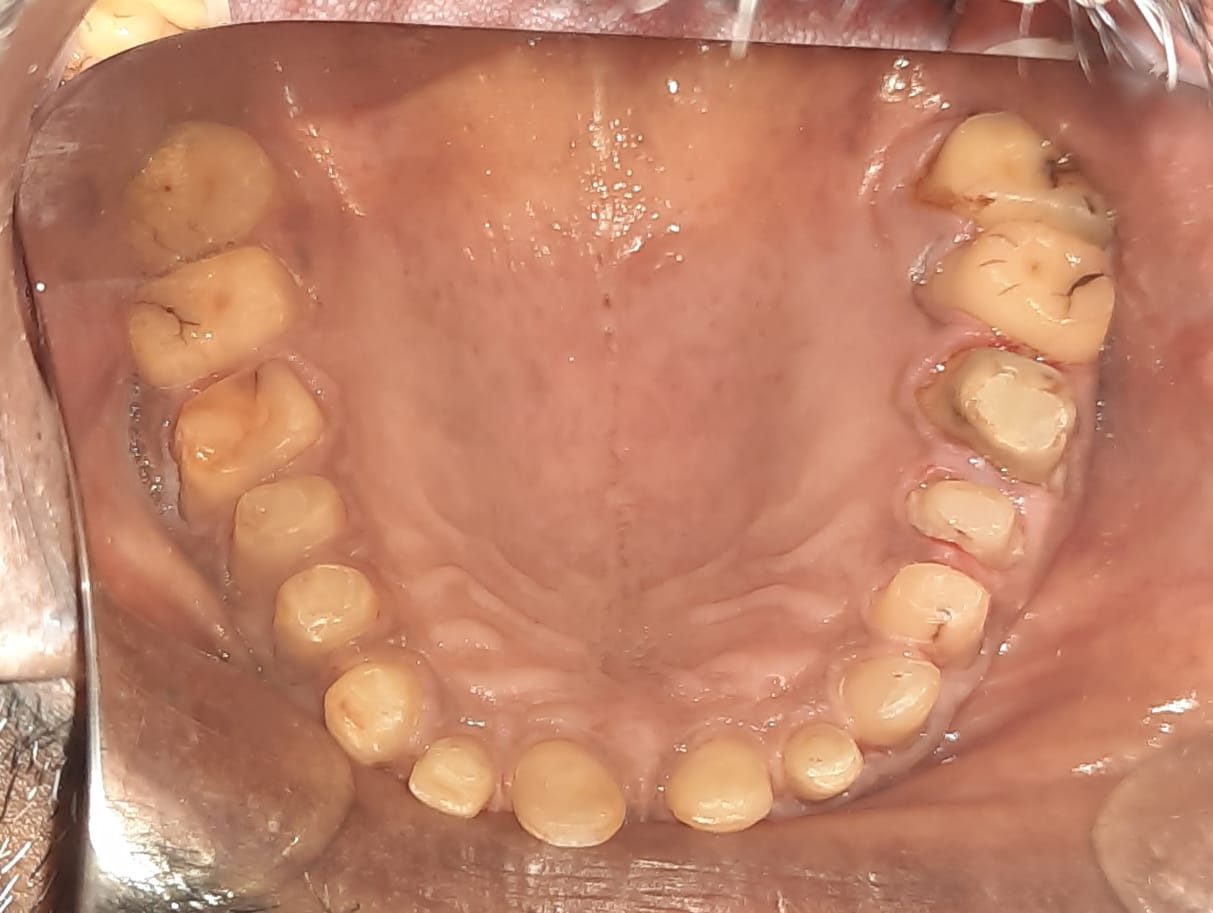

Patient wanted to get a new set of new teeth as old teeth were severely attrited and he was not able to chew. Medical history was taken and patient was fit for all the dental procedure. A detailed radiographic examination was conducted with the help of opg Treatment planning. A detailed case history along with radiological investigation and recording of of Bite of patient it was done in first visit. An appliance to relieve occlusion was given for 21 days Root canal treatment it was perform for all the teeth in subsequent visits. Occlusion was recorded using a specialised semi adjustable articulator. A temporary prosthesis was given to be used for or 15 days. A permanent Restoration was fabricated using pfm Crowns. A patience on patient end is a much needed thing as it involves time duration of of 1 to 2 months. Patient has to be absolutely serious about the treatment protocols which we are following as it involves use of appliances on patients end. Patient has to leave habit of eating Supari and tobacco as it was the cause in in severe reservation and attrition of teeth the artificial prosthesis is a finely crafted instrument that needs to be used with precision. so patients willingness and a positive mindset is Paramount in treating such cases.

Step 2: State-of-the-Art Treatments Experience top-notch root canal treatments and effective temporization protocols for optimal oral health.

Step 3: Precise Impressions Utilizing cutting-edge scanning technology, we ensure accurate impressions for a perfect fit.

Step 4: Exceptional Dental Lab Our second nature Dental lab crafts your dream smile with utmost precision.